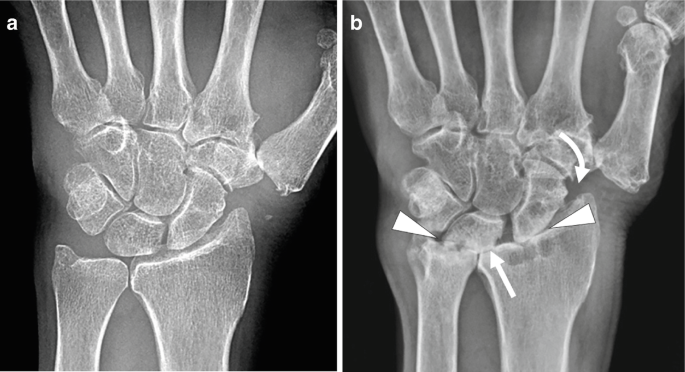

Distal radioulnar joint dislocation is an uncommon injury where the distal radius and ulna lose alignment, often caused by trauma, falls, or sports injuries. Patients typically present with wrist pain, swelling, deformity, and difficulty rotating the forearm. Diagnosis is made

A TFCC tear refers to injury of the triangular fibrocartilage complex, a key stabilizer of the distal radioulnar joint and ulnar side of the wrist. Tears can occur from acute trauma, such as a fall on an outstretched hand, or from chronic repetitive loading, particularly with

The DRUJ compression test evaluates for pathology at the distal radioulnar joint. With the forearm in a neutral position, the examiner compresses the ulna against the radius. The test evaluates for instability, tenderness, crepitus, or swelling and is compared to the